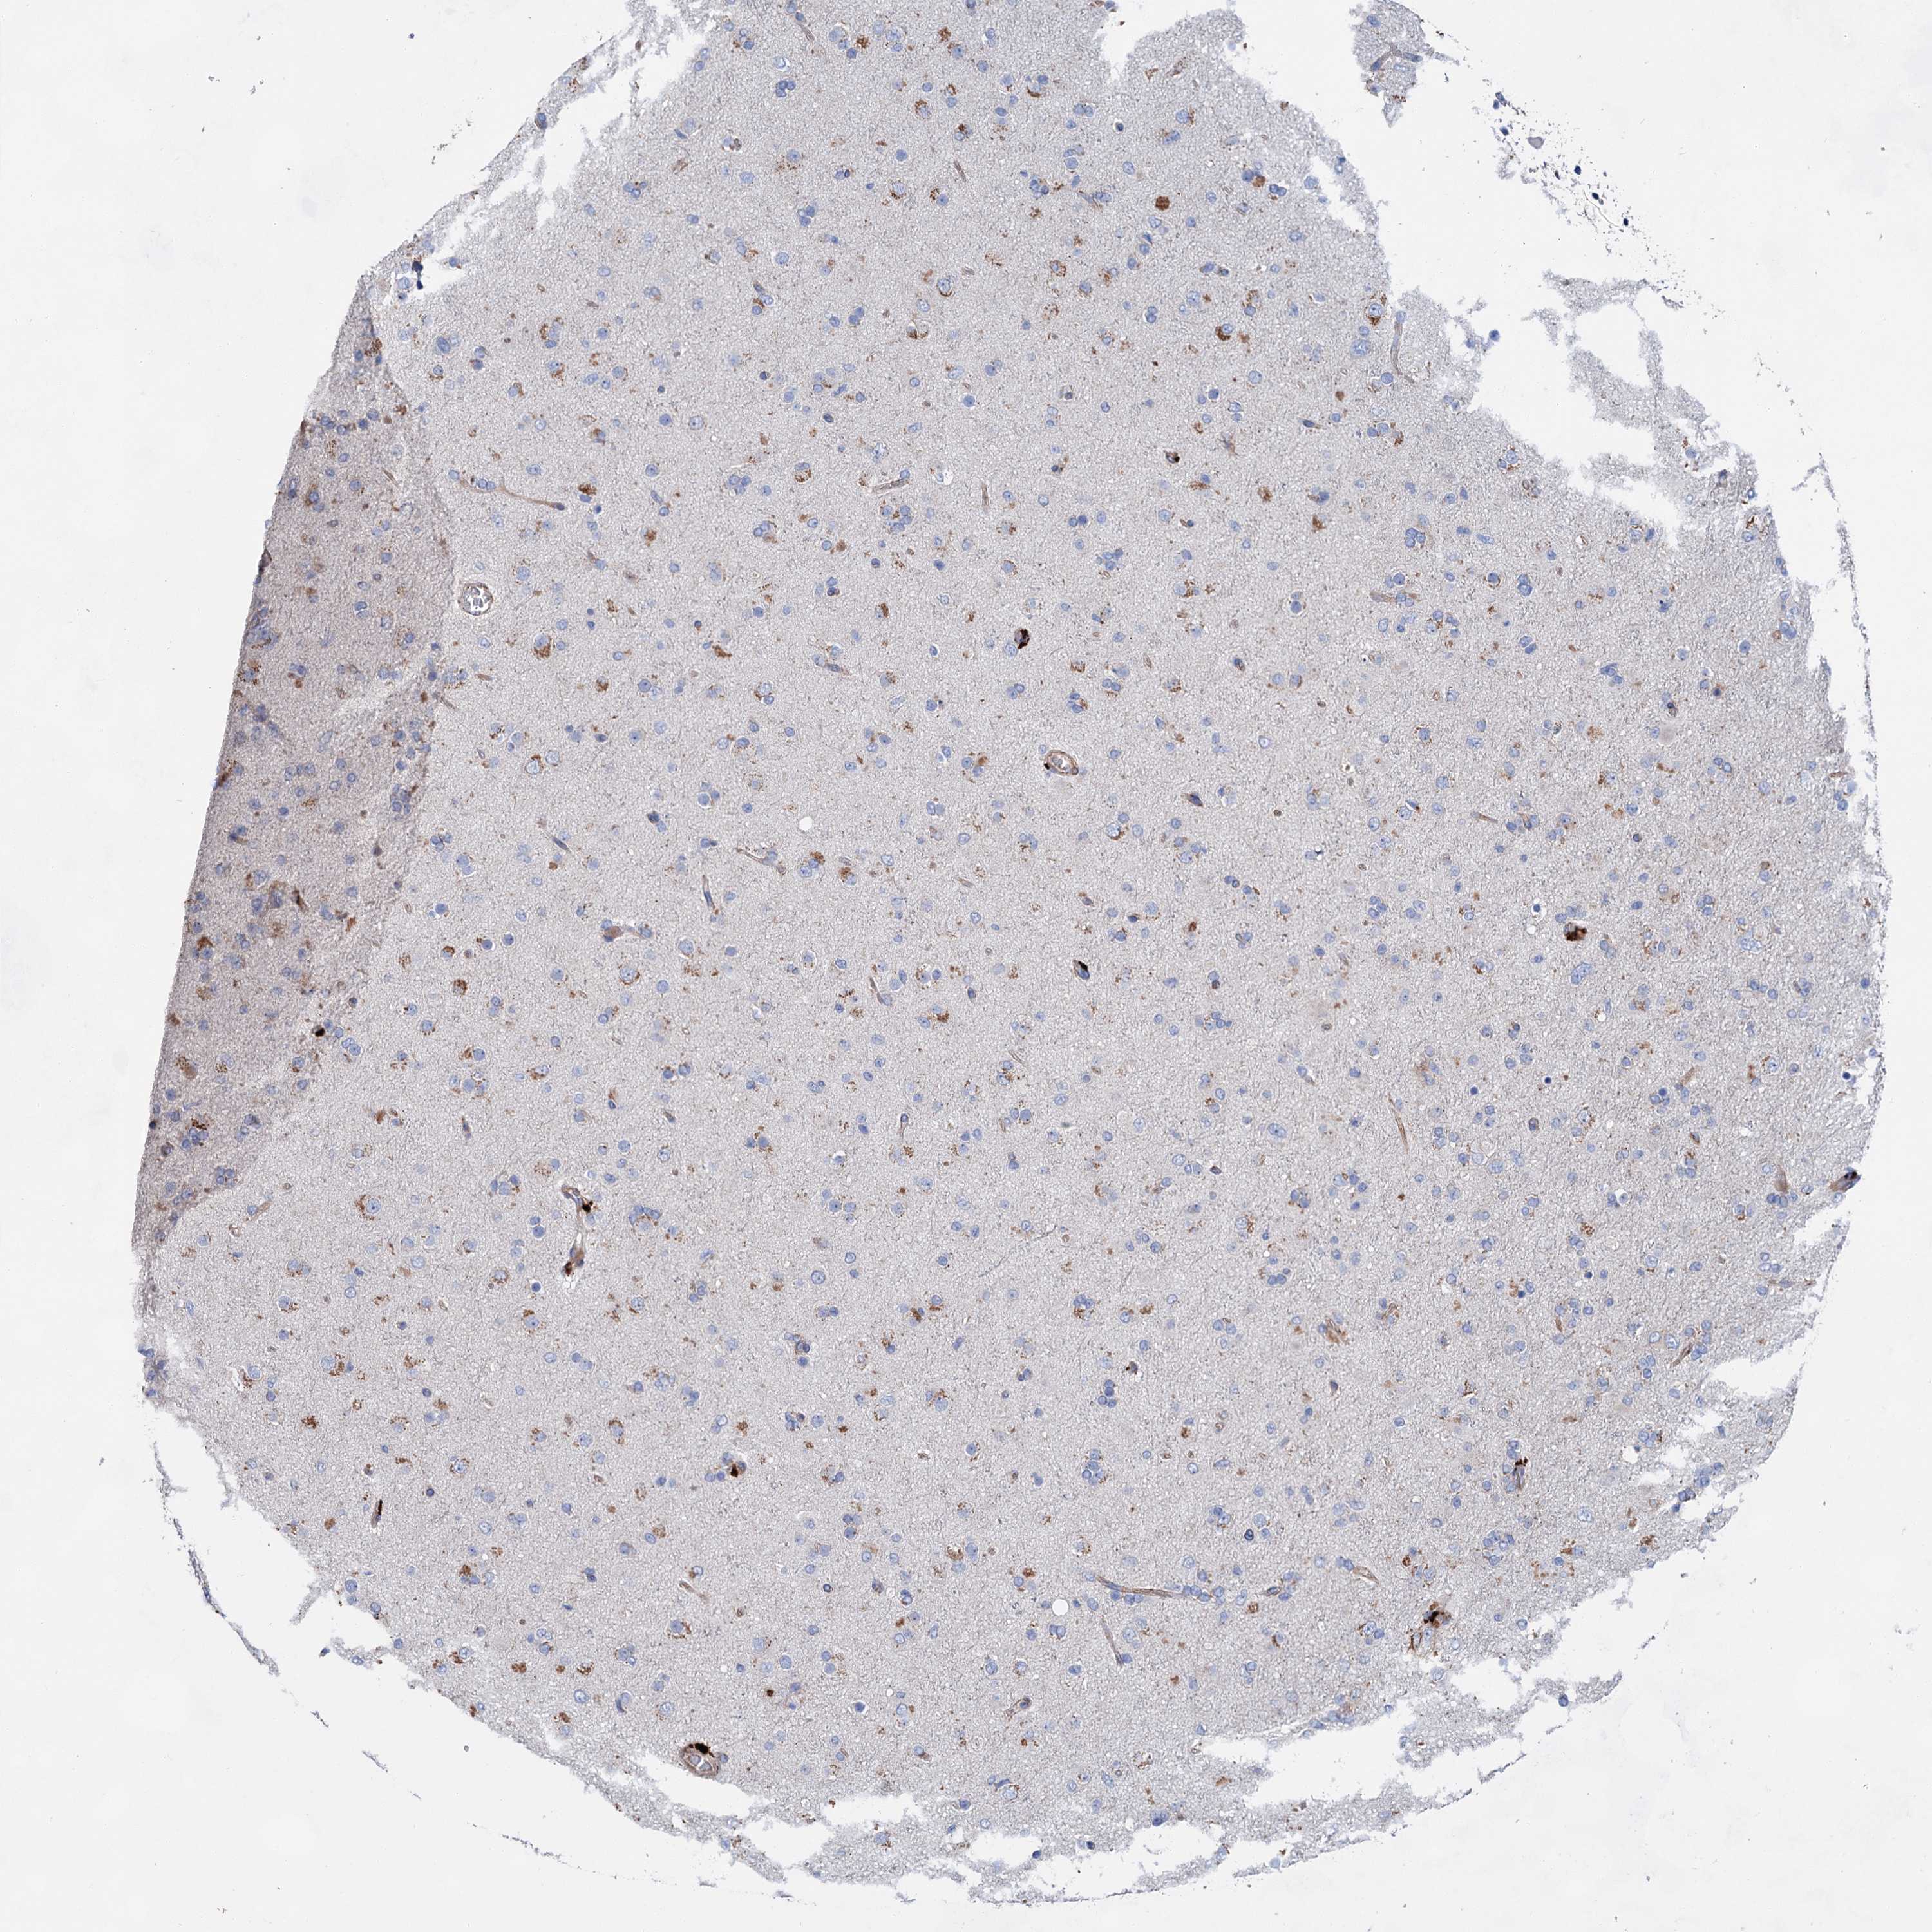

GLIOMA - Protein expressioni

A mouse-over function shows sample information and annotation data. Click on an image to view it in a full screen mode. Samples can be filtered based on level of antibody staining by selecting one or several of the following categories: high, medium, low and not detected. The assay and annotation is described here.

Note that samples used for immunohistochemistry by the Human Protein Atlas do not correspond to samples in the TCGA dataset.

Antibody stainingi

Antibody staining in the annotated cell types in the current human tissue is reported as not detected, low, medium, or high, based on conventional immunohistochemistry profiling in selected tissues. This score is based on the combination of the staining intensity and fraction of stained cells.

Each image is clickable and will lead to virtual microscopy that enables deeper exploration of all samples and also displays staining intensity scores, fraction scores and subcellular localization as well as patient and tissue information for each sample.

Antibody HPA036159

Antibody HPA057384

Staining

High

Medium

Low

Not detected

Intensity

Strong

Moderate

Weak

Negative

Quantity

>75%

75%-25%

<25%

None

Location

Nuclear

Cytoplasmic/membranous

Cytoplasmic/membranous,nuclear

Glioma, malignant, High grade

Glioma, malignant, Low grade

Glioblastoma, NOS

Glioma, malignant, NOS